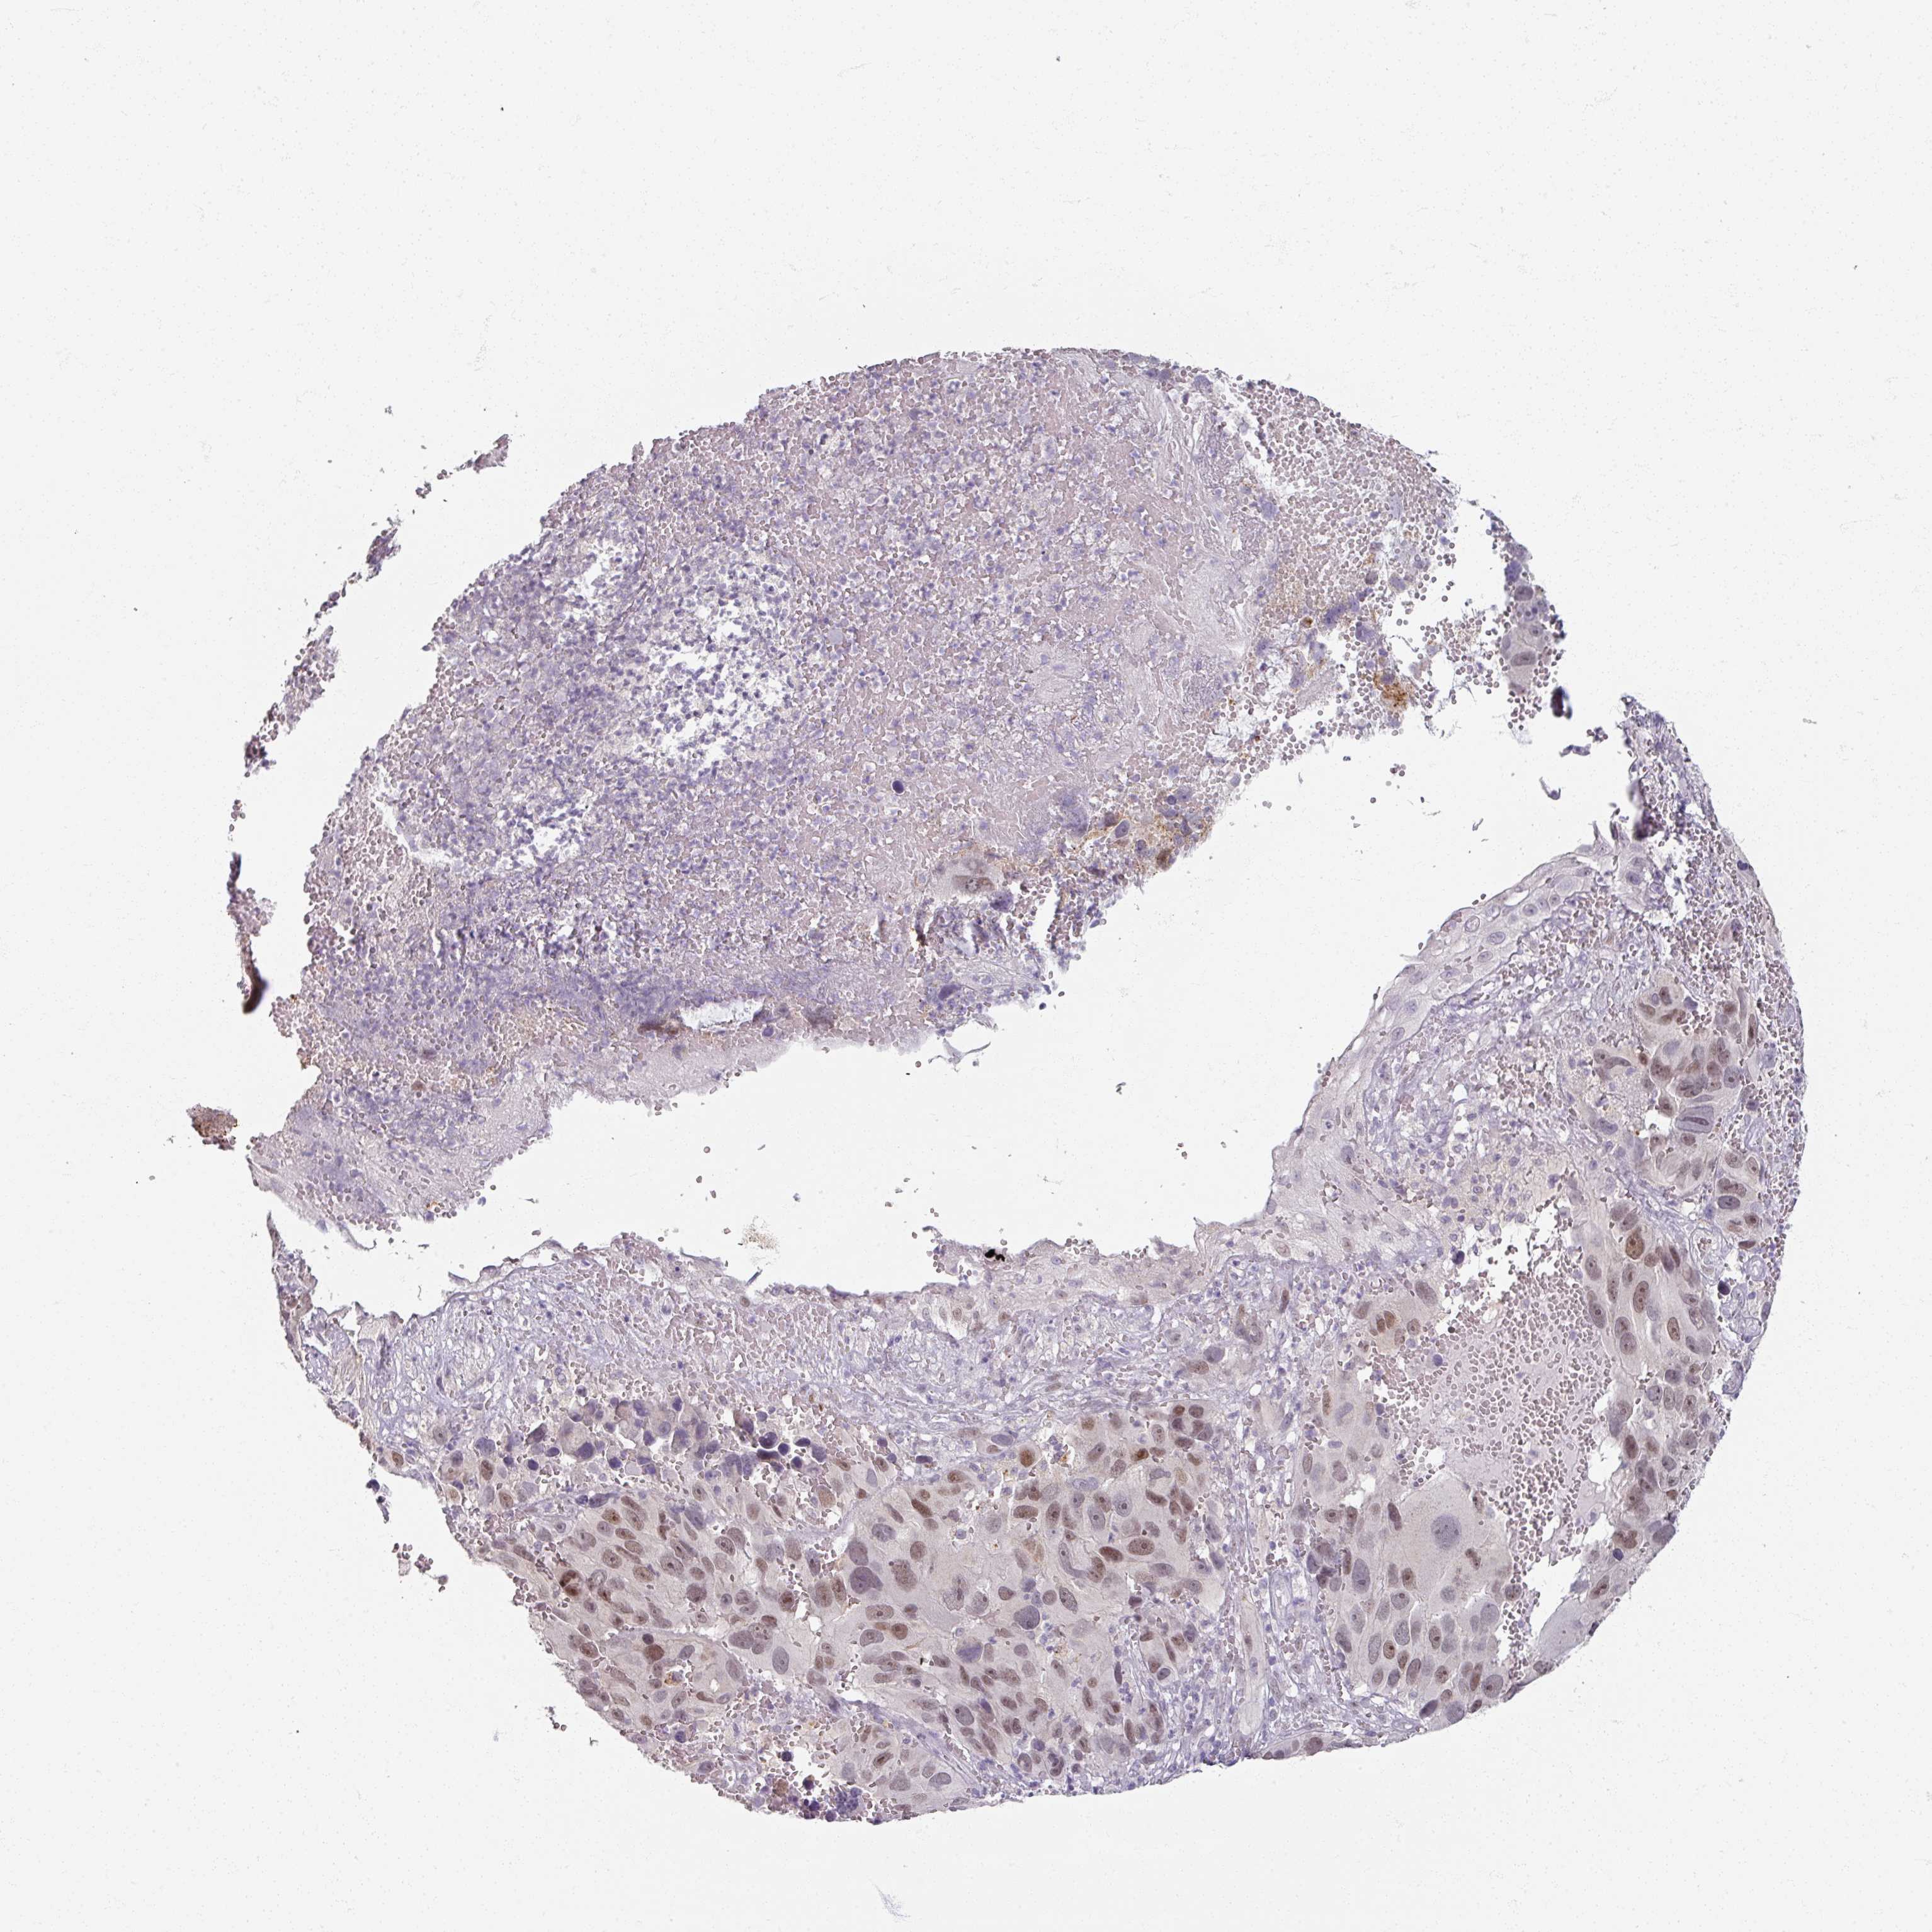

MELANOMA - Protein expressioni

A mouse-over function shows sample information and annotation data. Click on an image to view it in a full screen mode. Samples can be filtered based on level of antibody staining by selecting one or several of the following categories: high, medium, low and not detected. The assay and annotation is described here.

Note that samples used for immunohistochemistry by the Human Protein Atlas do not correspond to samples in the TCGA dataset.

Antibody stainingi

Antibody staining in the annotated cell types in the current human tissue is reported as not detected, low, medium, or high, based on conventional immunohistochemistry profiling in selected tissues. This score is based on the combination of the staining intensity and fraction of stained cells.

Each image is clickable and will lead to virtual microscopy that enables deeper exploration of all samples and also displays staining intensity scores, fraction scores and subcellular localization as well as patient and tissue information for each sample.

Antibody HPA000536

Antibody CAB056152

Antibody CAB056153

Staining

High

Medium

Low

Not detected

Intensity

Strong

Moderate

Weak

Negative

Quantity

>75%

75%-25%

<25%

None

Location

Nuclear

Cytoplasmic/membranous

Cytoplasmic/membranous,nuclear

Malignant melanoma, NOS

Malignant melanoma, Metastatic site